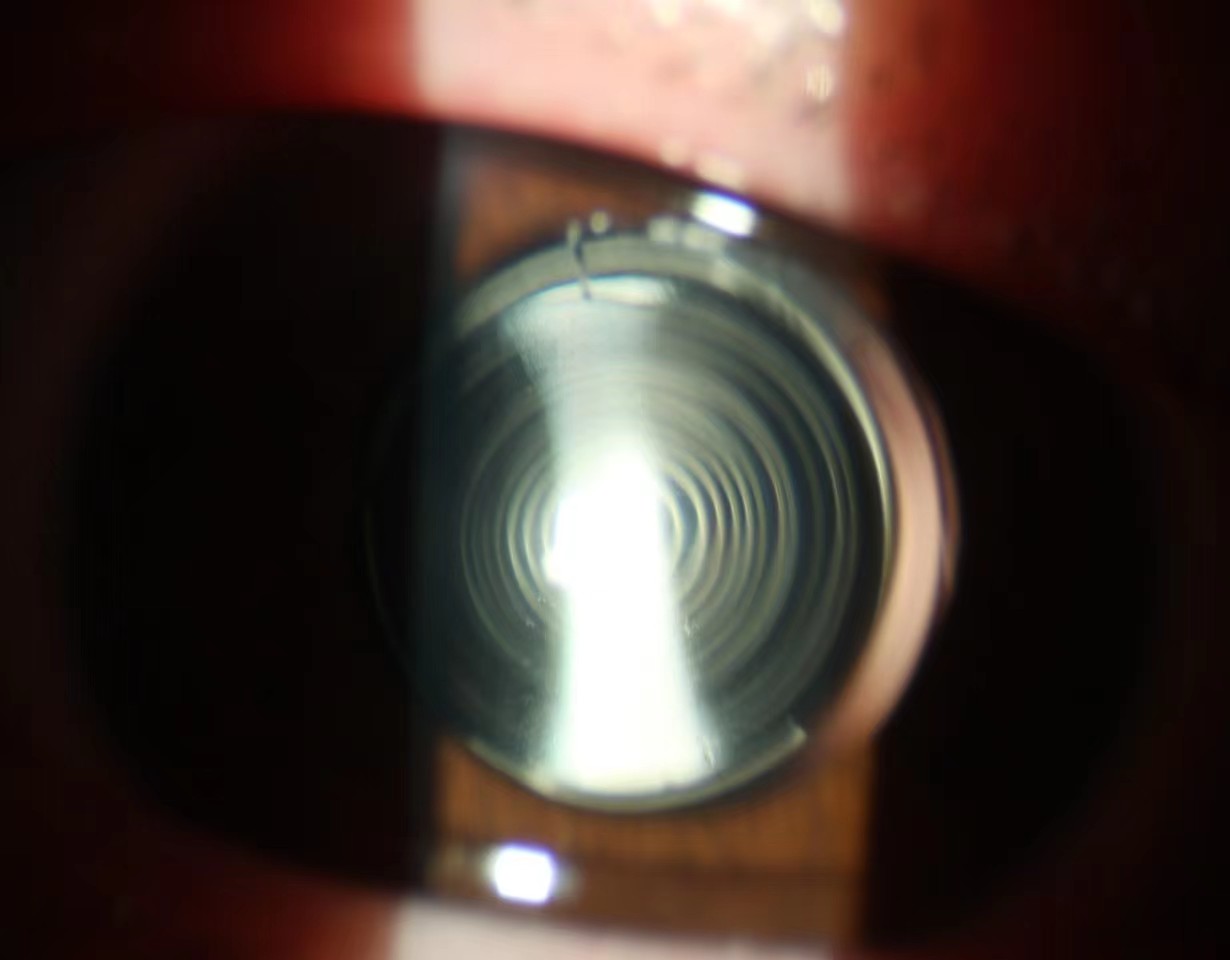

患者是一名19岁的高三学生,因右眼先天性白内障的困扰暂停学业到黑料网眼科就诊。由于患者需要术后尽快能够投入学习中,术前沟通中流露出对术后视力很高的期望,希望术后不但能够看远而且能够近距离连续阅读。此类患者常规的解决方案是使用多焦点人工晶体恢复术后远、中、近视力,但术前检查发现患者双眼均有350度以上的散光,不符合常规多焦点人工晶体植入的适应证。面对患者和家属殷盼的目光,经过讨论、重复测量和反复验算,为患者采取超声乳化白内障吸除联合双焦点散光型人工晶体植入手术,同时根据先天性白内障不确定因素备用了单焦点人工晶体植入术联合术后眼镜矫正的替补方案,最终在手术室和麻醉科配合下张坚主任主刀,仅用时15分钟即顺利完成手术。次日晨患者术眼残余散光不足25度,人工晶体光学中心与瞳孔中心重合,散光轴位与术前设计的100°角度分毫不差,恢复的远视力达1.0,中视力和近视力均为0.8,完美的达到术前预定恢复视力脱镜的效果。

目前白内障手术从复明手术发展到屈光性白内障手术,患者不但要求能看到,还要看得清和看得舒适。功能性人工晶体解决患者这些需求应运而生,主要包括散光型人工晶体和多焦点人工晶体,其中散光型人工晶体主要矫正患者术前较大散光以提高裸眼视力,手术前要进行眼表散光标志的标记,术中严格按术前计算标记的轴位将人工晶体置于指定轴线位置;而多焦点人工晶体则是为了改变单焦晶体不能远近视力兼得的缺点,要求患者自身光学条件良好,术中人工晶体中心定位良好。该患者自身光学特性不能满足常规多焦点人工晶体要求,需联合散光矫正才能获得满意作用,而散光型多焦点人工晶体设计制造同样复杂,目前仅有双焦点散光型人工晶体在临床应用,该类人工晶体度数计算牵涉因素多,术中操作复杂,不但要对齐瞳孔中心、光学中心,还要对齐散光轴线,对术前测量、设计计算及手术团队要求很高。